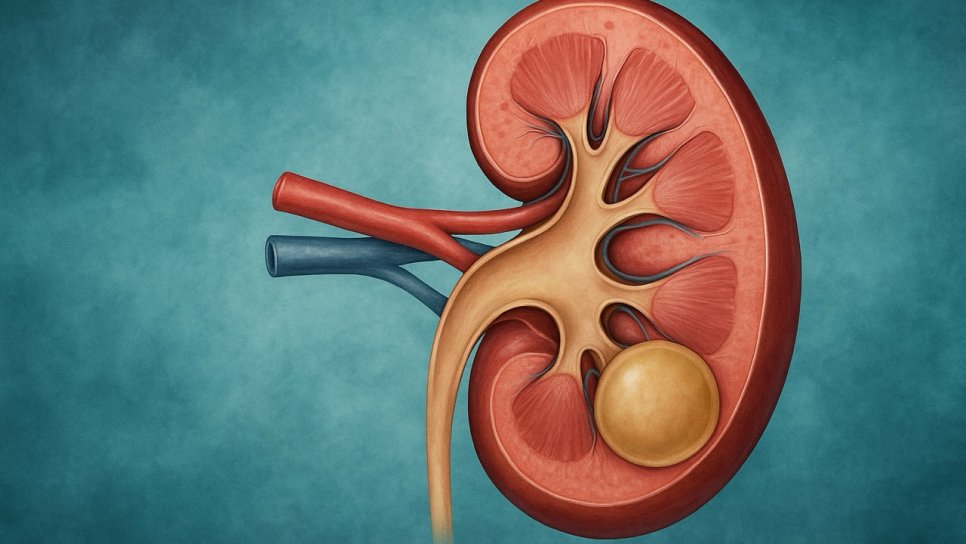

Bosniak sınıflaması, böbrek kistlerini anatomik ve radyolojik özelliklerine göre beş temel sınıfa ayırır. Bu sistem, hem görüntüleme teknolojilerinin evrimine paralel olarak güncellenmiş hem de klinik karar algoritmalarını yönlendiren güçlü bir çerçeveye dönüşmüştür.

Bu sınıflama, lezyonun duvar kalınlığı, iç yapısı, kontrast tutma durumu ve solid bileşen içerip içermemesine göre yapılır. Aşağıda her sınıf ayrıntılı olarak açıklanmıştır.